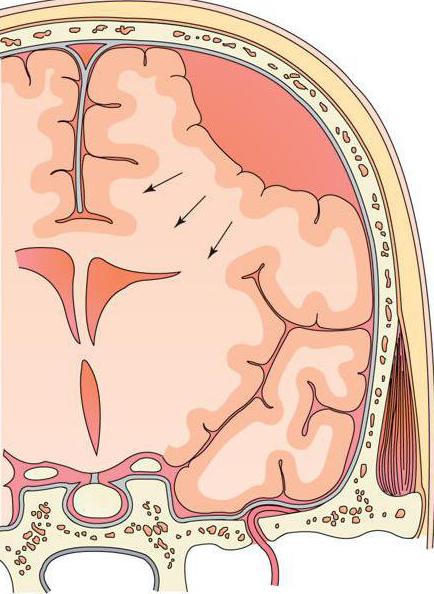

Внутричерепные кровоизлияния у новорожденных презентация - 92 фото